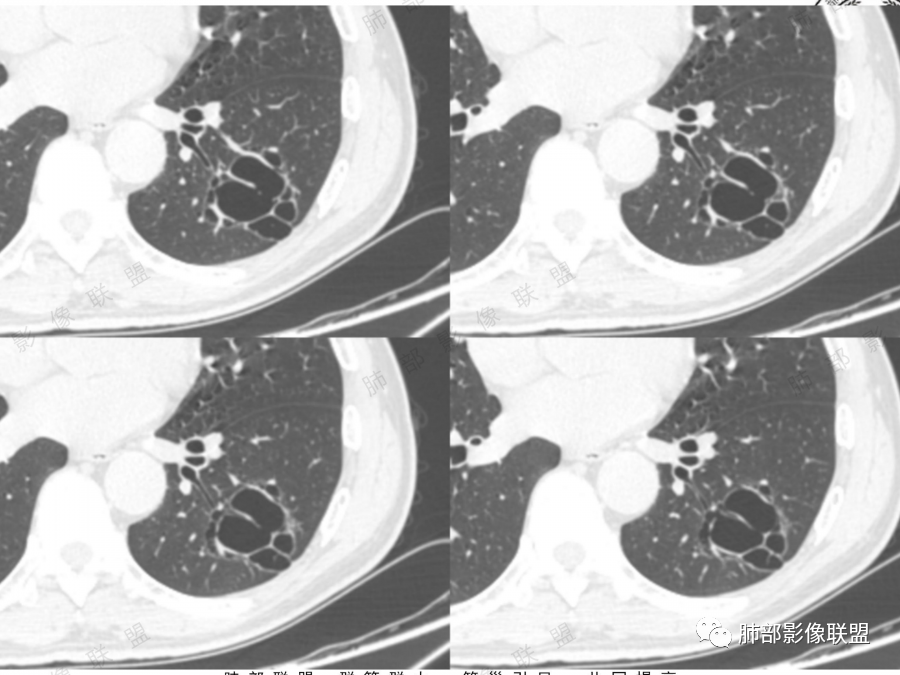

图一看到支气管堵塞,不知道是不假象

图二图三似见毛玻璃

另外分隔比较光滑似无壁结节。

目前可疑恶性,但是证据不足,毛玻璃不够,壁结节及分隔增厚结节不明显。怎么处理,要么随访,如果觉得忍不了也可以切。不会太耽误

6.动态随访观察:初期囊腔病灶未出现明显恶性征象时诊断有困难,但是仍要引起足够的重视对病灶密切定期随访,如果随访中囊腔增大、囊壁不规则增厚、壁结节增大、囊腔消失呈实性病灶均应及时手术治疗。